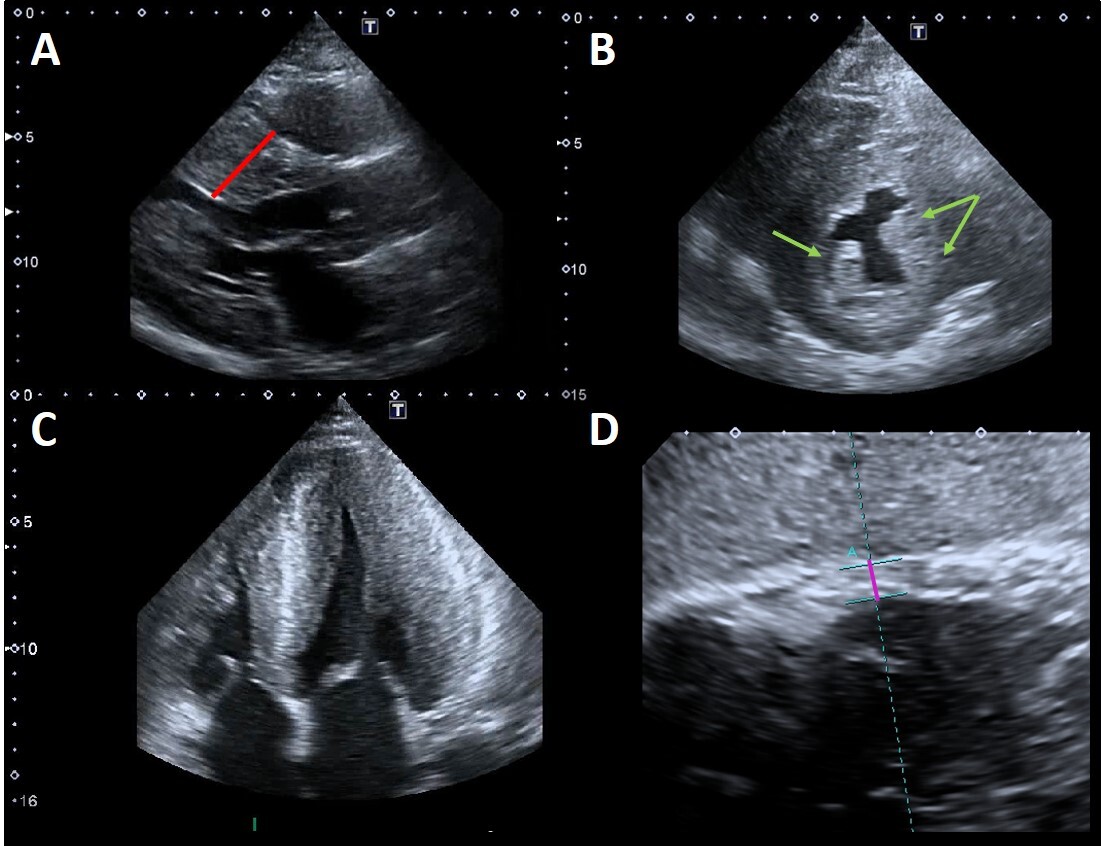

LV systolic function, as measured by ejection fraction (EF), is generally preserved in patients with FD until advanced stages of the disease (Fig. 3A).

Fig. 3.Example of Fabry cardiomyopathy with normal LV ejection fraction (LVEF) but impaired indexes of longitudinal systolic function. (A) Apical four chambers view: LVEF 65% measured by biplane Simpson method; (B, C) Tissue Doppler mitral annular velocities at lateral and septal corners respectively, showing low systolic velocities (6.5 cm/s at both sides); (D) 2D speckle tracking analysis bull’s-eye plot, showing reduced LV-GLS value (–15%).

However, longitudinal systolic function [41] can be affected in the early stage of cardiac involvement (Fig. 3B–D). Most FD patients without LVH undergoing echocardiography are gene-positive patients in whom the presence of cardiac involvement needs to be addressed. The distinction between “overt Fabry cardiomyopathy” (i.e., LVH) and latent cardiac involvement represents a crucial issue with strong impact on the therapeutic management, as guidelines and recommendations on FD suggest starting ERT as soon as any evidence of organ damage is detected.

Pieroni et al. [41] compared Tissue Doppler (TD) velocities of patients with Fabry mutations plus LVH (genotype positive/phenotype positive) vs patients with Fabry mutations without LVH (genotype positive/phenotype negative) and healthy controls. They showed that both systolic and diastolic TD velocities were statistically significant lower in patients with Fabry mutation without LVH compared to healthy controls, suggesting that decreased values of both lateral and septal S’ and e’ have a high sensitivity and specificity for identifying Fabry patients without LVH. The specificity and sensibility of these findings were partially confirmed lately [42] but it is now clear that impaired TD velocities are useful to differentiate gene-carriers of hypertrophic phenotypes vs normal or athlete’s heart [43].